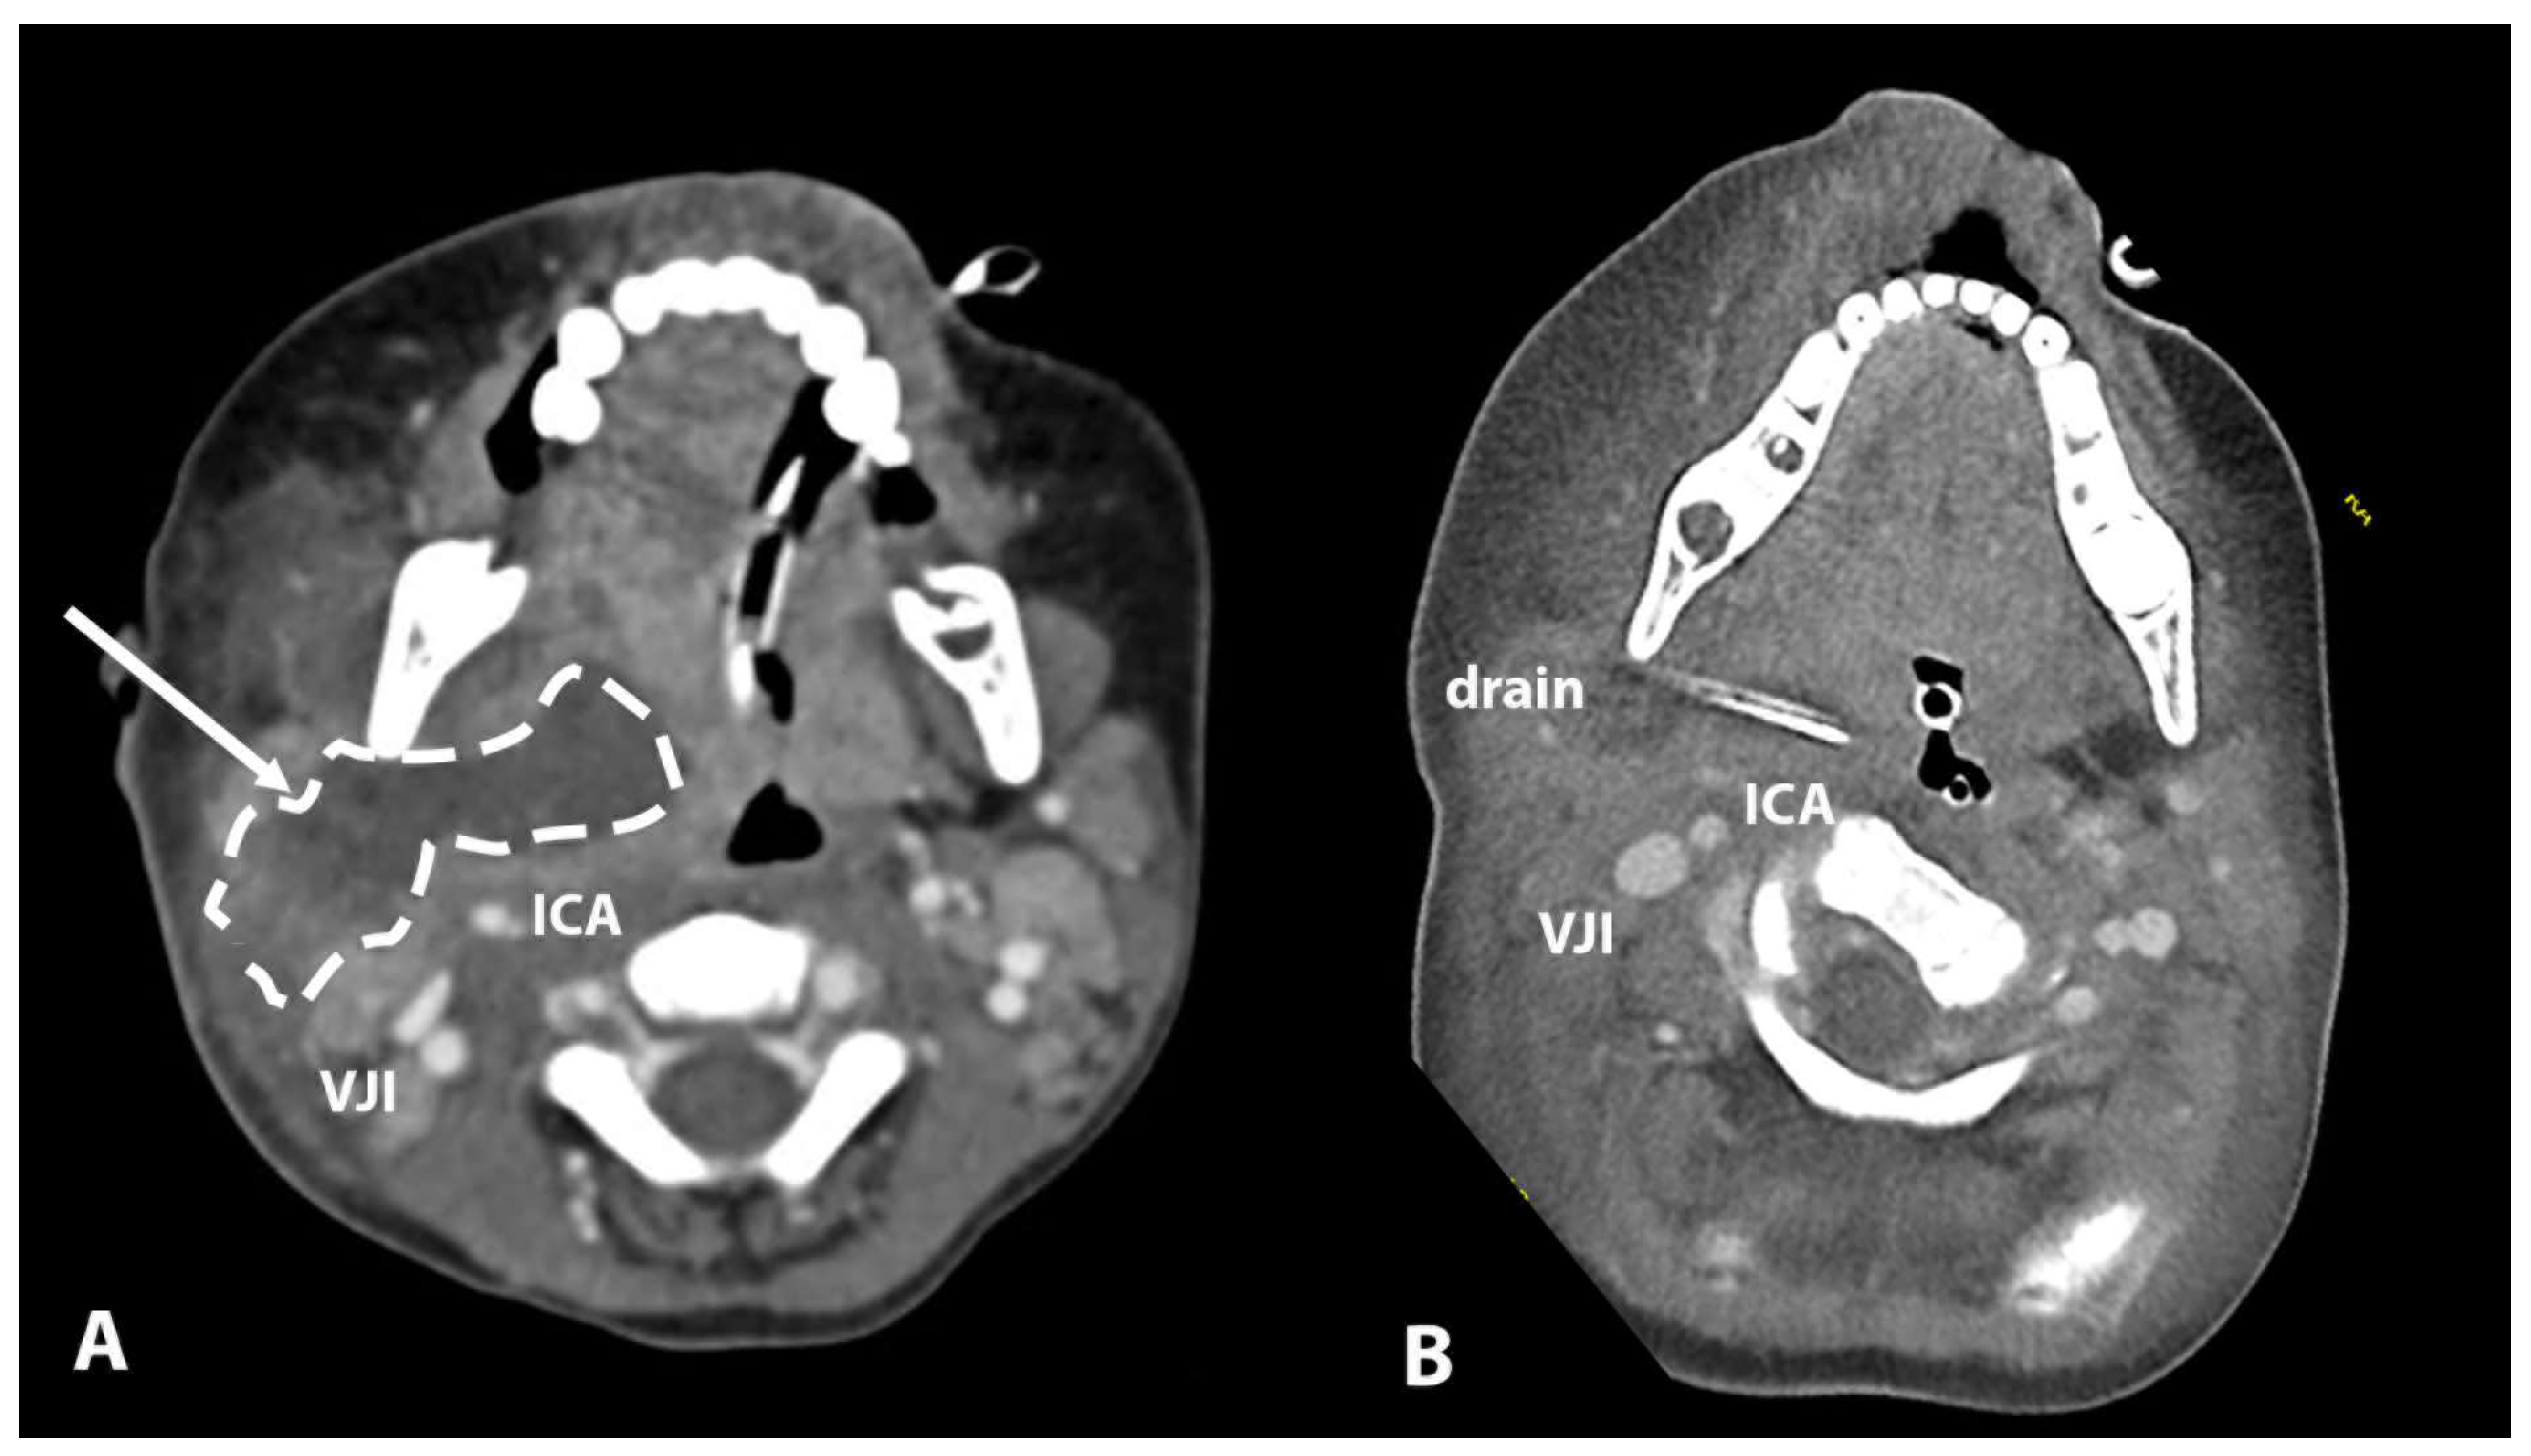

| 6 | 3 years | Parapharyngeal | Conglomerate of enlarged level II lymph nodes, area of collection in level II lateral to ICA | Major parapharyngeal collection 53 × 25 × 45, lateral and anterior to ICA | / | Intubation | Lateral | CT |

| 6 | 3 years | Parapharyngeal | Lateral | Intubation | Transcervical incision | Image guidance | Staph. aureus | Piperacillin/Tazobactam | 4 |